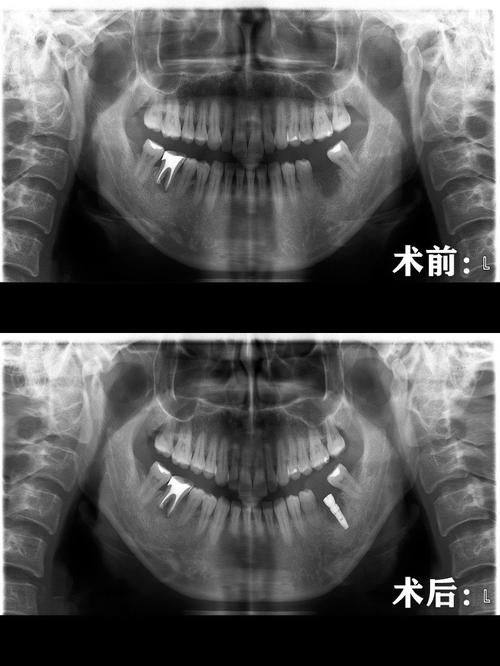

5. 种植牙:种植牙是一种较为精良的牙齿修复方式。张亚科医生在种植牙领域有着深入的研究和丰富的实践经验。他能够正确地评估患者的口腔条件,选择合适的种植体,并进行精细的种植手术。在种植过程中,他注重手术的安心性和成功几率,术后还会为患者提供详细的护理指导,确保种植成效良好。

3. 患者赵先生:我因为牙齿缺失,想做种植牙。张亚科医生在手术前给我做了全方面的检查,详细地向我介绍了种植牙的过程和注意事项。手术过程中,他操作非常熟练,我几乎没有感觉到疼痛。术后,张医生还为我提供了详细的护理指导,让我能够更好地修复。现在我的种植牙已经完全修复,功能和美观都和真牙一样。张亚科医生的技术和服务都让我非常满意,我会向身边的人推荐他。